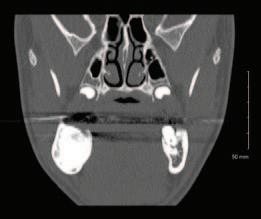

2. Wright, J.T., Crall, J.J., Fontana, M., Gillette, E.J., Nový, B.B., Dhar, V., et al Evidencebased clinical practice guideline for the use of pit-and-fissure sealants: a report of the American Dental Association and the American Academy of Pediatric Dentistry. J Am Dent Assoc 2016; 147 (8): 672-682.e12.

3. Lygidakis, N.A., Garot, E., Somani, C., Taylor, G.D., Rouas, P., Wong, F.S.L. Best clinical practice guidance for clinicians dealing with children presenting with molar-incisorhypomineralisation (MIH): an updated European Academy of Paediatric Dentistry policy document. Eur Arch Paediatr Dent 2022; 23 (1): 3-21.

4. Frencken, J.E. The state-of-the-art of ART sealants. Dent Update 2014; 41 (2): 119-120, 122-124.

CLINICAL TIPS

FIGURE 2: Effective cotton wool roll isolation. FIGURE 3: Conditioning of the pits and fissures. FIGURE 4a: Application of a GI sealant (GC Fuji IX). FIGURE 4b: Manipulation into the pits and fissures using the ‘finger press’ technique.

30 Journal of the Irish Dental Association | February/March 2023: Vol 69 (1)

FIGURE 5: GI fissure sealant.

A sagittal split osteotomy approach for removal of a large cementoblastoma at the mandibular angle

Précis

This case report demonstrates the effectiveness of sagittal split osteotomy in the removal of a mandibular cementoblastoma.

Abstract

Benign lesions at the angle of the mandible are frequently removed by a conventional intra-oral approach to gain access and achieve complete visualisation. This method is quick and effective when dealing with small, benign lesions that are superficially located at the angle of the mandible. The removal of large and deeply located lesions with a conventional intra-oral approach, however, brings about a unique set of challenges, particularly when the third molar is displaced towards the inferior border of the mandible, including: lack of complete visualisation of the lesion; difficulty in identification and protection of the inferior alveolar nerve; and, the necessity of removing a considerable amount of osseous structure, thus increasing the risk of a mandibular fracture. Alternative techniques for such lesions include an extra-oral approach, but this could potentially create a cosmetic defect from cutaneous scarring and can result in facial nerve injury.

This case report describes the use of a unilateral sagittal split osteotomy (SSO) in the removal of a mandibular cementoblastoma. This is a safe and effective technique allowing optimal access to the tumour with complete visualisation, identification and protection of the inferior alveolar nerve, and with minimal bone removal, while maintaining mandibular integrity, strength and facial aesthetics.

Introduction

A cementoblastoma, also referred to as a true cementoma, is a rare, benign odontogenic tumour arising from ectomesenchymal cells.1 They have also been referred to in the literature as: sclerosing cementoma; peri-apical fibroosteoma; and, peri-apical fibrous dysplasia. Disorganised proliferation of cementoblasts results in subsequent deposition of cement-like tissue around the roots of teeth. Cementoblastomas account for between 0.69% and 8% of all odontogenic tumours and tend to occur between the second and third decades of life, with a median age of 20 years and an age range of eight to 44 years. Some studies show no gender preference,2 while others show a higher rate of occurrence in males.3 Cementoblastomas tend to occur more frequently in the posterior mandible, involving the roots of premolar and

molar teeth. They are asymptomatic lesions, which demonstrate a slow and expansile growth, and are usually discovered as an incidental radiographic finding.4 However, cortical bone expansion can result in facial asymmetry and symptomatic painful lesions when facial nerves become involved.5 Because cementoblastomas have unlimited growth potential, treatment includes tumour resection with the extraction of the associated tooth. If the tumour is small at the time of diagnosis, treatment may consist of surgical removal with endodontic therapy and retention of the involved tooth. The traditional surgical approach for excision of a cementoblastoma at the mandibular angle is removal of bone to gain access to the tumour. However, the surgical risk increases with removal of larger lesions via traditional techniques, which will involve the removal of larger amounts of bone,

PEER-REVIEWED

Journal of the Irish Dental Association February/March 2023; 69 (1): 31-35

BA APsych BDS NUI MFD RCSI MB BCh BAO Surgical SHO

BDS

FFDRCSI

Registrar in Oral and Maxillofacial Surgery South Infirmary Victoria University Hospital Cork

FDS

in Oral and Maxillofacial Surgery South Infirmary Victoria University Hospital Cork Corresponding author: Dr Mar Cotter. E: mcottdentist@gmail.com Journal of the Irish Dental Association | February/March 2023: Vol 69 (1) 31

Dr Mar Cotter

Mr Zeeshan G. Khattak

MSc OMFS MFDS RCPS